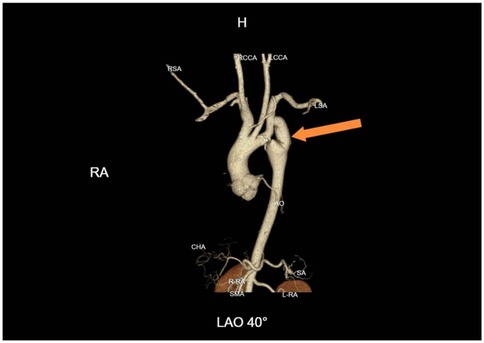

After surgery, the patient's antihypertensive regimen was gradually reduced in a stepwise fashion. At discharge, only metoprolol was continued, and both nifedipine and sacubitril/valsartan were discontinued. Postoperative blood pressure measurements were balanced across all four limbs: 115/69 mmHg (right upper limb) and 126/75 mmHg (left lower limb). Follow-up CTA confirmed satisfactory graft patency and flow (Figure 3).

Figure 3

Immediate postoperative CTA following subclavian-to-descending aorta bypass. Patency of the synthetic vascular graft (Dacron) from the left subclavian artery to the descending aorta is demonstrated, with normalization of the aortic lumen distal to the coarctation.

After more than six months of follow-up observation, the patient reported complete resolution of cardiopulmonary and neurological symptoms. Blood pressure remained well controlled, and there was no recurrence of symptoms. Serial imaging demonstrated continued graft patency without evidence of complications such as graft occlusion, pseudoaneurysm, infection, or aneurysmal progression (Figure 4). Additional axial CTA images are provided (Figure 5) to better illustrate the extent of aortic calcification.

Figure 4

One-year follow-up CTA demonstrating graft patency. Continued patency of the bypass graft with no evidence of pseudoaneurysm, graft occlusion, or aneurysmal progression at the coarctation site.